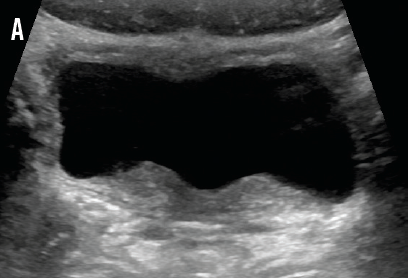

Sheela Madipelli, MD

At the initial newborn examination at 2 hours of age, swelling and ecchymosis of the right side of the scrotum of a newborn boy was noted.